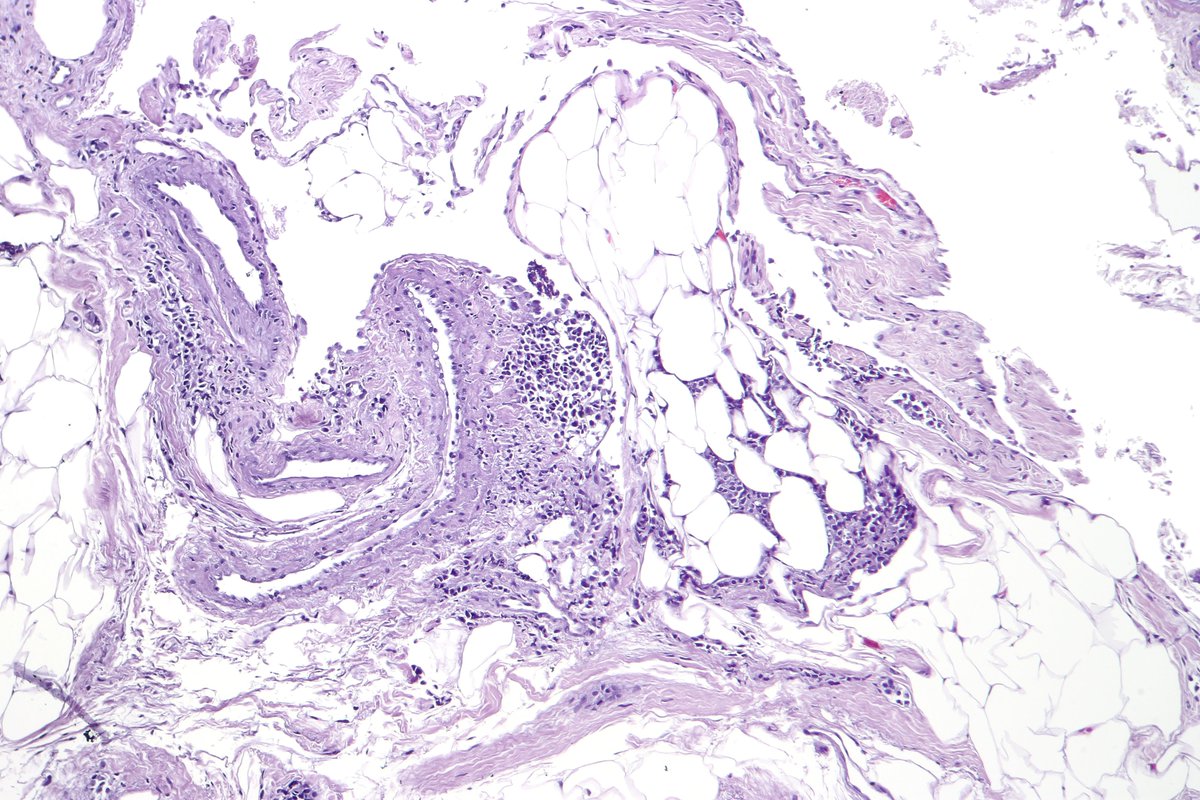

Fetal testis (14 weeks) showing primitive tubules with germ cells surrounded by interstitial Leydig cells. #pathology #pedipath